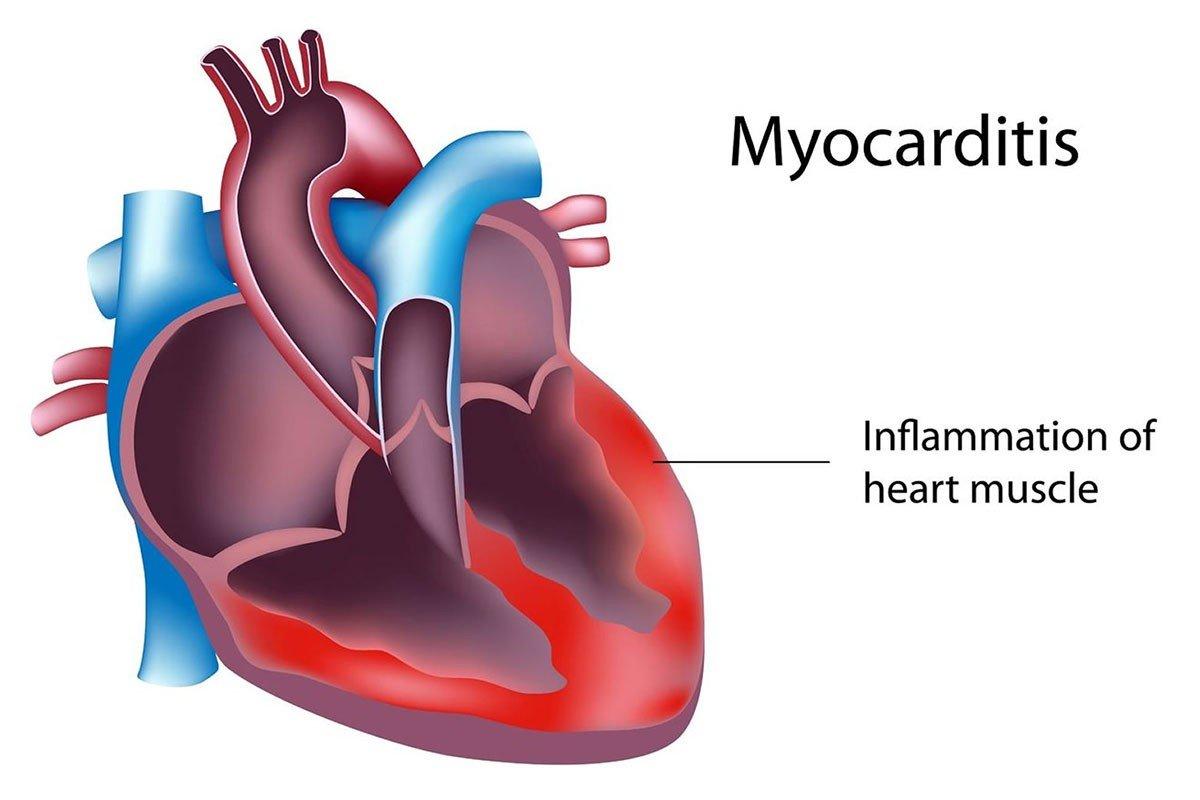

میوکاردیت یک بیماری التهابی است که عضله قلب را تحت تأثیر قرار میدهد. این بیماری میتواند به دلایل مختلفی از جمله عفونتها، بیماریهای خودایمنی و حتی برخی داروها ایجاد شود. در این مقاله، به بررسی جامع میوکاردیت، علائم، علل، تشخیص و درمان آن میپردازیم.